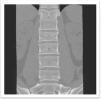

Los estudios de gabinete mostraron fractura bifocal multifragmentada de olécranon izquierdo y de cúpula radial in situ AO 21-C2.1, fractura y avulsión de cóndilo humeral AO 13-B1.1, fractura en sacro transforaminal izquierda in situ grado 2 de Dennis, avulsión de la tuberosidad del isquion izquierdo AO 61-A1.3 y fractura de L2 AOSpine A3, N0 (figs. 1 y 2).

El control tomográfico mostró anormalidades congénitas en T12 (hemivertebra) y L1 con una diastematomielia de tipo I. También se observó fractura A3 en L2 sin invasión a canal medular.